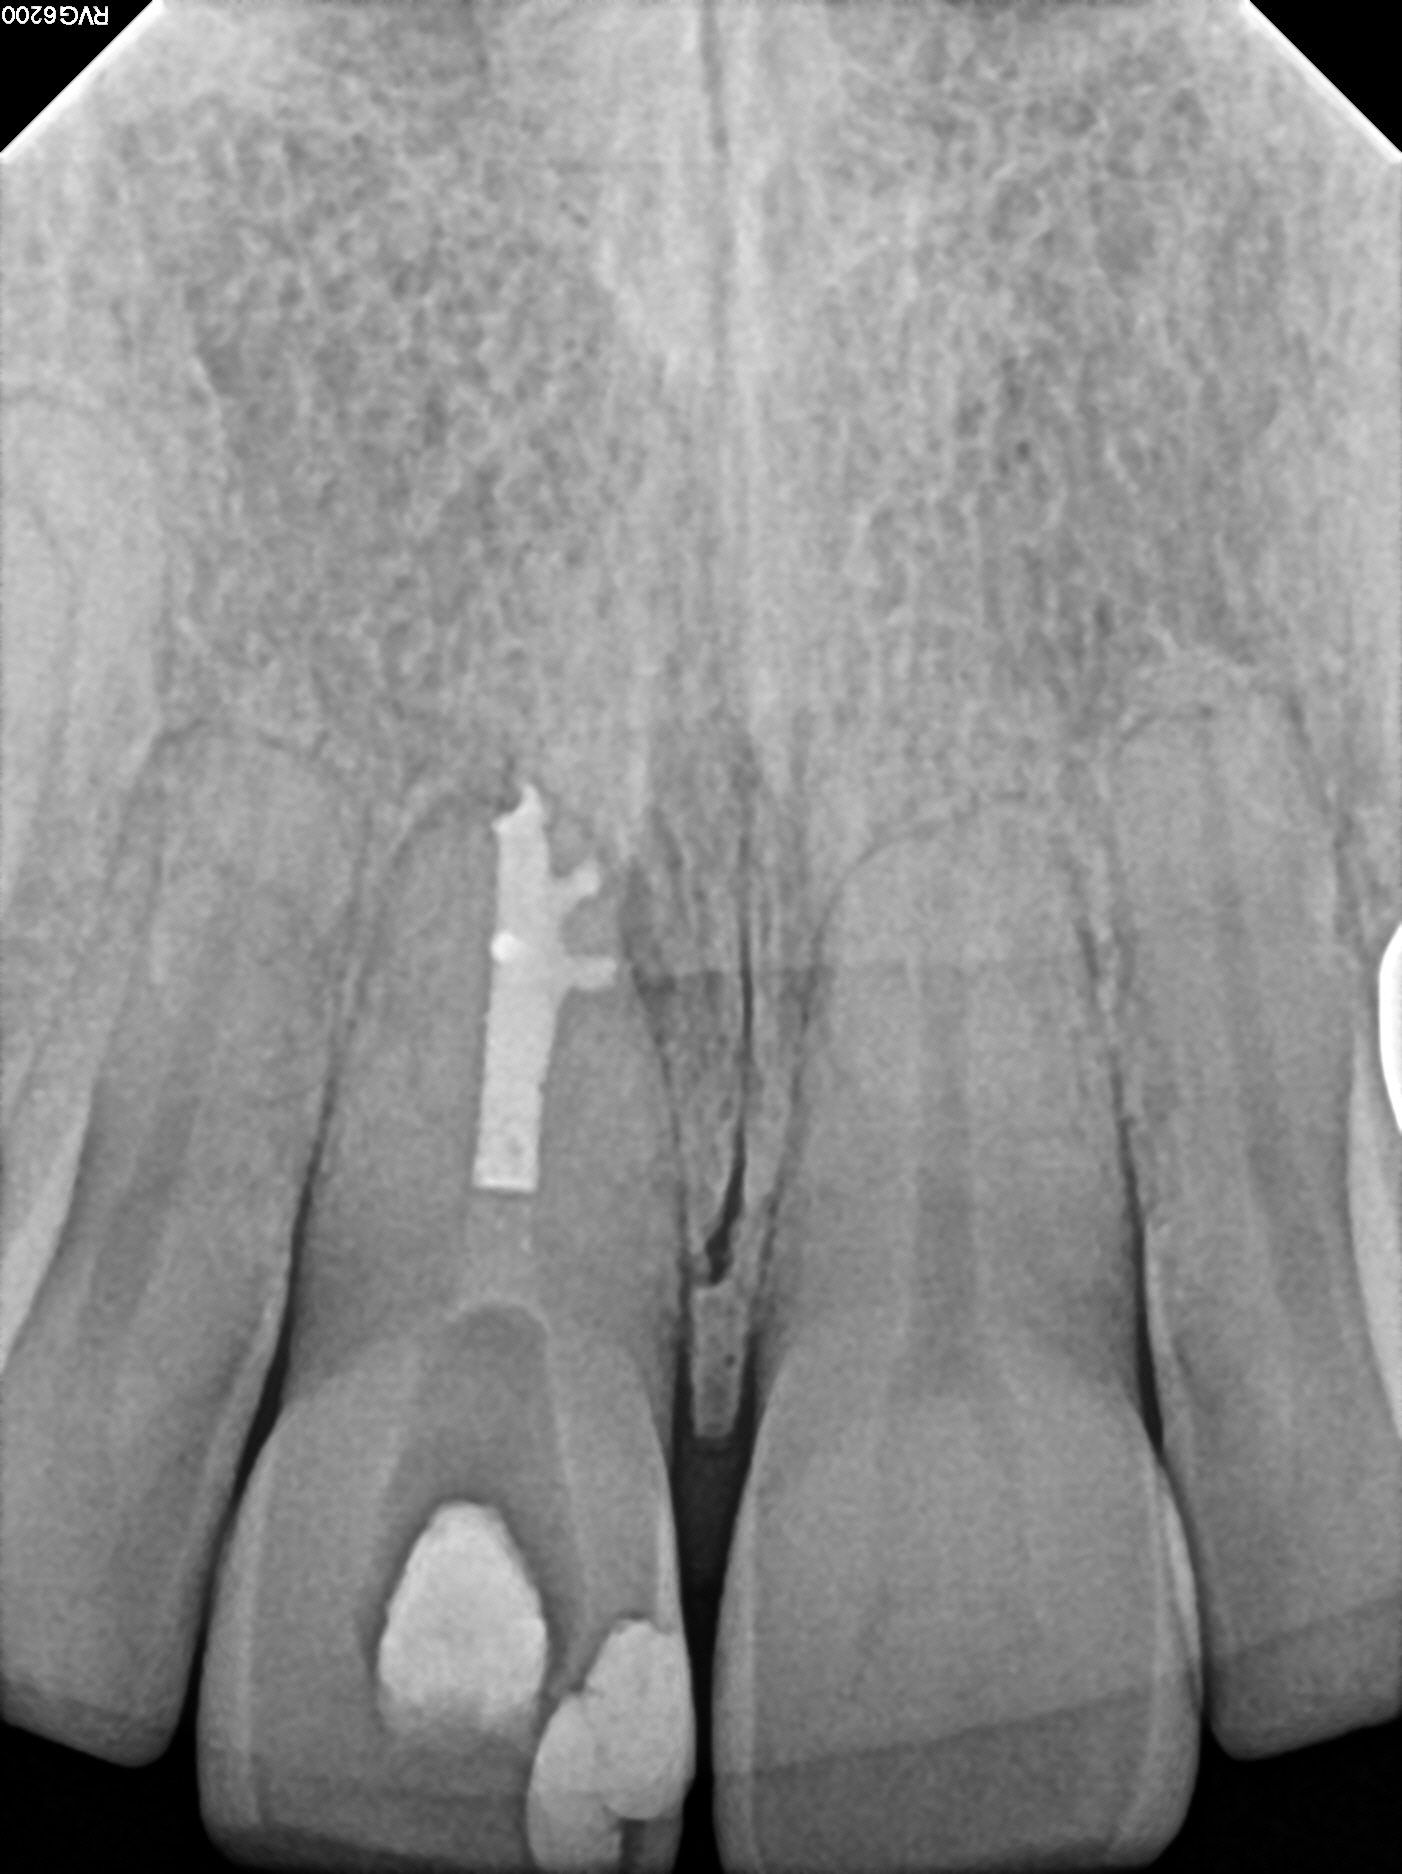

Case 1

This case shows two upper front teeth, #7 and #8, that were both contributing to the large infection. This infection eroded away the bone above the tooth in a "through-and-through" manner, meaning that the thicker, outer layer of bone on the palate side and also on the lip side of the jaw bone was eroded away. The picture on the left is a pre-treatment image, and the picture on the right is 5 years later, showing complete healing. The body is perfectly happy with these two teeth, evidenced by the bone directly in contact with the roots.